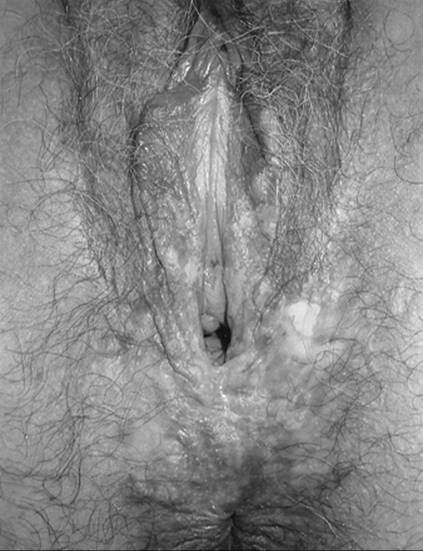

Patients with VIN most commonly present with pruritis and vulvar lesions. These lesions may appear scaly, white, red, or hyperpigmented (Fig. 51.1, Fig. 51.2, Fig. 51.3 and Fig. 51.4). Careful inspection with 5% acetic acid and liberal use of punch biopsy are the cornerstones of diagnosis. An underlying malignancy may be present in 7% to 22% of patients who undergo surgical excision for vulvar carcinoma in situ. Wide local excision with at least a 5-mm margin is the preferred management option as it allows pathologic confirmation and is associated with less morbidity than skinning vulvectomy. Skinning vulvectomy with split thickness skin graft may be an option in patients with widespread disease. Laser ablation is also an effective nonmutilating option in patients with multifocal or clitoral disease. Recurrences are frequent (10%–50%) despite negative surgical margins and therapy should be tailored to symptom control and ruling out underlying malignancy. Patients should be followed every few months with careful visual inspection of the vulva and taught self-exam skills as well.

FIG. 51.1. Vulvar carcinoma in situ presenting as white or hyperpigmented lesion. See color figure 51.1.

FIG. 51.2. Vulvar carcinoma in situ before application of 5% acetic acid. See color figure 51.2.

FIG. 51.3. Vulvar carcinoma in situ after application of 5% acetic acid. See color figure 51.3.